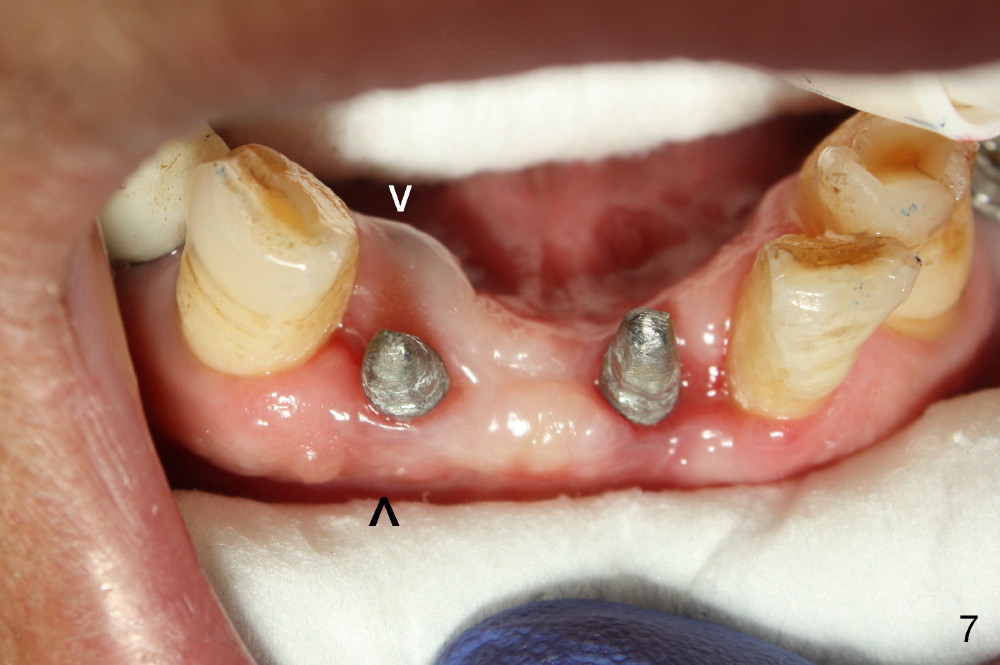

Fig.7 shows these two one piece implants immediately prior to cementation of the FPD (Fig.8). They are much more parallel to each other after prep, as compared to Fig.6. Fig.9 shows apparent bone growth around #24 implant (at the crest) 6,9 months post cementation and surgery, respectively. Orthodontic treatment will incorporate the fixed partial denture. Fig.10 shows that bone grows coronally (arrow) to cover 3 threads (from #6 thread to #3) at the site of #24 one year after functioning. There is mild buccal gingival infection involving #26 retainer. Preop CBCT is reviewed to determine whether it is related to potential thread exposure. It appears that at the sites of #24 (Fig.13,14) and 26 (Fig.11,12), 2.5 mm implant is more appropriate for the narrow ridge than 3.0 mm one. In fact, periimplantitis develops at #26 two years of absence of perio maintenance (because of atrial fibrillation with blood thinner; Fig.15, 3 years 7 months post cementation). Periimplantitis persists 4.5 months later. Although water pik is purchased, it is not used often because of low blowing force. If needed, remove the FPD atraumatically. Unwind the implant, clean the coronal threads with Titanium brush or remove the exposed threads and replant the implant with bone graft.